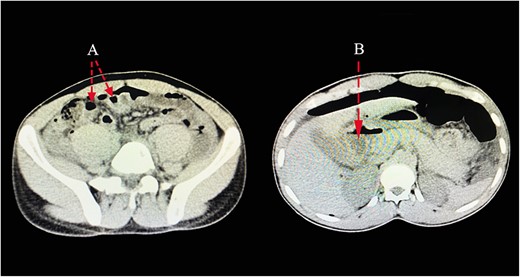

A 23-year-old male patient was sent to our emergency department from a nearby hospital. He arrived with a week’s history of cramping lower abdomen discomfort, mostly in his right lower quadrant and radiating to his back, that began gradually and worsened with time. During the course, the illness was associated with recurrent low-grade fevers and a single episode of vomiting that contained previously consumed meals. His bowel habits, however, remained unchanged. He was clinically stable when he arrived, with blood pressures of 124/73 mmHg, pulse rates of 87 bpm and saturating well on room air. He had a regular abdominal contour that moved in sync with his breathing. On palpation, there was mild discomfort with guarding along his right and left iliac as well as umbilical aspect. On percussion across the epigastric and umbilical region, there was a normal tympanic tone, and typical bowel sounds were appreciated. His full blood count indicated that he had increased neutrophils, but his electrolytes were normal. An NGT placement was commenced. A provisional of acute appendicitis was obtained along with differential diagnoses of a ruptured appendix with peritonitis and perforated peptic ulcer. An abdominal computed tomography (CT) scan with contrast revealed pneumoperitoneum related to a perforation, with free fluid collection in the abdomen and a thickening of the pyloric antrum measuring ~1.3 cm (Fig. 1). Abdominal USS identified symptoms of an appendix rupture. An explorative laparotomy was imminent. Following a midline abdominal incision, the abdomen was incised in layers. There was a liter of turbid peritoneal fluid and several immature adhesions, an inflamed retrocecal appendix and multiple fibrin exudates, which were observed in the cecum and right paracolic gutter, with stomach contents reaching the appendiceal aspect. A 0.5 × 0.2-cm perforation was discovered on the pyloric antrum at the anterior region of the lesser curvature. An appendectomy was done after adhesion lysis and a tissue sample was taken for histology. Modified Graham’s technique was used to repair the perforation. Abdominal lavage with copious amounts of fluids was done, drains were placed and the fascia and skin were sealed with Nylon sutures (Fig. 2). Post-operatively, the patient had a quick recovery and was discharged after 5 days. Subsequently, the patient’s follow-up assessments were unremarkable.

CT scan images pointing out presence of pneumoperitoneum related to a perforation (A), with free fluid collection in the abdomen (B).